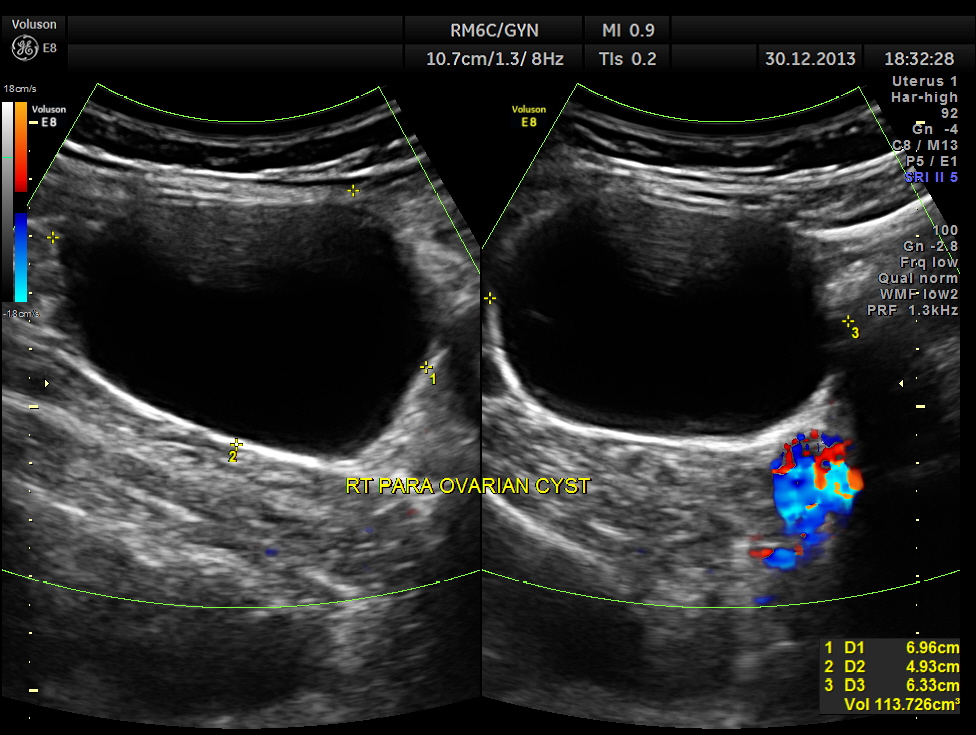

A para ovarian simple cyst was seen in the right adnexal region separate from the right ovary.

This patient had a GB Polyp ( which would explain her dyspepsia ) and a right PARA OVARIAN simple cyst ( which would explain her right lower quadrant colicky pain ).